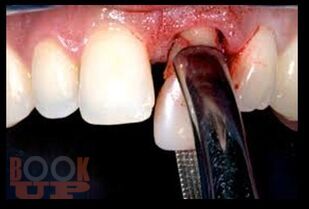

В предлагаемом учебном пособии рассмотрены основные вопросы местного обезболивания, применяемого в стоматологической практике на амбулаторном прием. Приведены характеристики современных местноанестезирующих препаратов и пути их введения. Описаны и продемонстрированы в иллюстрациях ряд хирургических стоматологических операций.